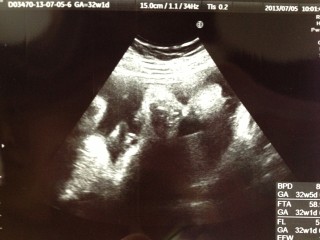

写真:32w1d:ケイトさん:こんなに開いたパー

なかなかお顔を見せてくれない息子ちゃん、今日のエコーでは手のひらを大きく開いてパーをして顔を隠していました(笑)先生もこんなに開いたパーをは珍しいね、と言ってくれました(^^)